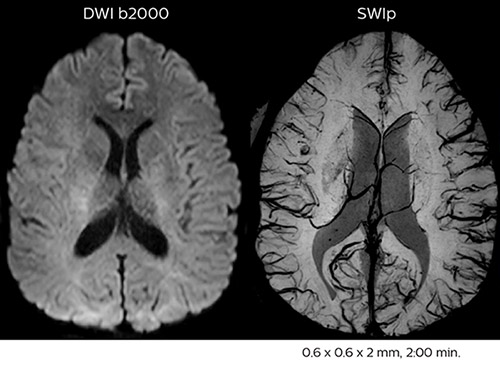

Improved diffusion imaging in stroke patients

Using MultiBand SENSE allowed the staff to improve their diffusion quality. “Our diffusion sequence was already fast before, about 40 seconds. Now with Elition, it still lasts 40 seconds, but we improved the spatial resolution by 0.2 mm and use high b-values to be more sensitive to visualize changes related to acute stroke,” says Dr. Savatovsky.

“We now also developed a high resolution DTI sequence (1.3 x 1.3 x 2 mm) that can be reformatted and takes 2 to 5 minutes depending on the coverage. We use it every time we have a doubt, or when we expect the diffusion to be abnormal but don’t see that on the fast sequence. We occasionally spot small ischemic infarctions that would not have been visible with the regular diffusion sequence.”

Fast acute stroke protocol

This is an example of acute ischemic stroke with distal occlusion of the right posterior cerebral artery. Note the improved visibility of the ischemic territory on the diffusion weighted image with high b-value. The 3D FLAIR shows a distal PCA occlusion. The fast SWIp depicts the thrombus on the isolated second echo image. The total scan time (including SmartBrain, preparations and a fast 3D T1w TSE Gd) is 8:00 minutes.